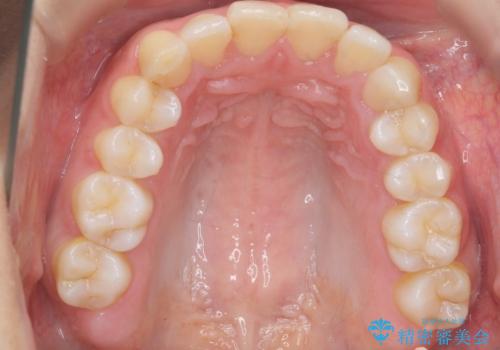

治療にも大変満足していただきました。

リファインメントも1回で済んでいます。